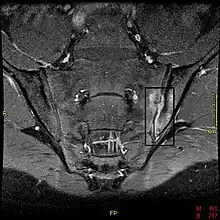

34-year-old male with AS. Inflammatory lesions of the anterior chest wall are shown (curved arrows). Inflammatory changes are seen in the lower thoracic spine and L1 (arrows).